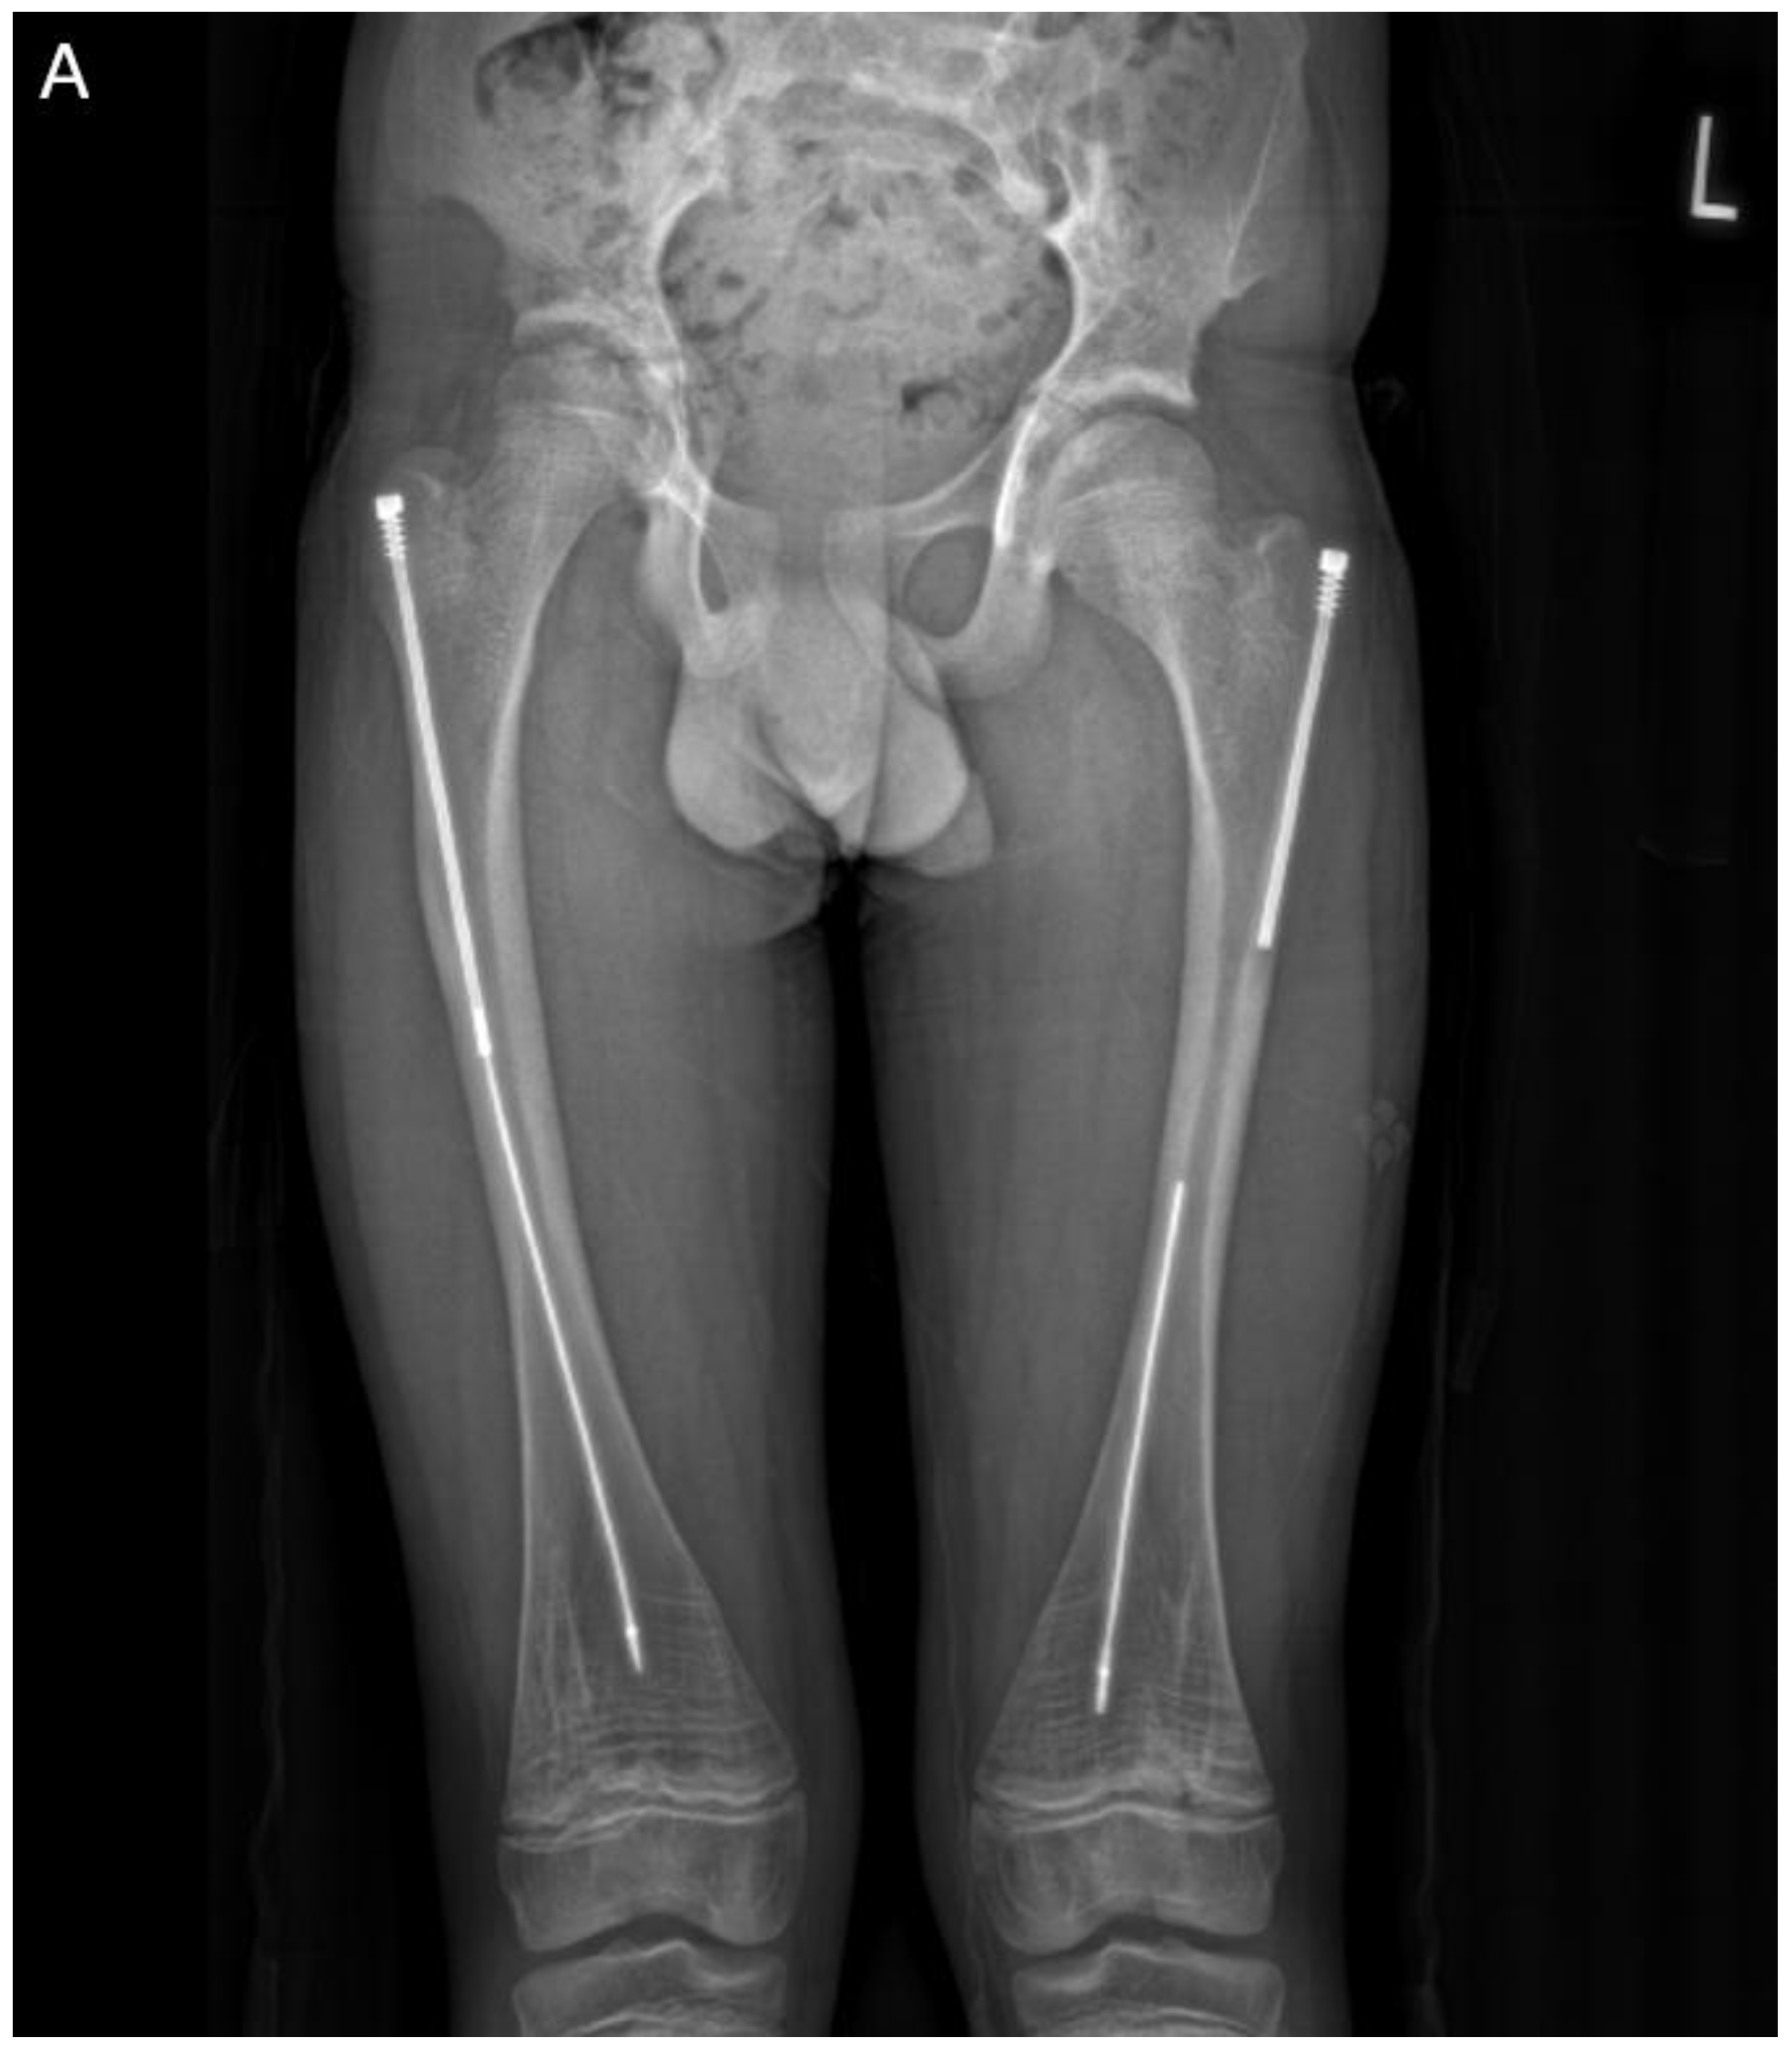

Figure 8. Preoperative and intraoperative X-rays of the lower extremities showing tibia deformities/fractures. Blue arrows indicate the CORAs.

In the first case, a three-year-old skeletally immature girl diagnosed with OI type III presented for surgical correction of significant right tibial bowing using a SLIM nail. After identifying the CORA (Figure 8), an anterior opening-wedge osteotomy was performed at the midshaft of the right tibia to realign the bone (Figure 9A). The proximal canal was sequentially reamed from the osteotomy site to accommodate the SLIM nail, and a medial parapatellar approach was used to retrieve the reamer at the level of the knee (Figure 9B-C). The distal tibia was similarly reamed up to the distal physis (Figure 9D-E). The SLIM nail was inserted through the knee and positioned centrally within the canal with good bony contact on all sides, with the proximal threading positioned in the epiphysis (Figure 9F-H). Fluoroscopy confirmed excellent alignment, and no additional internal fixation was needed. In this case, the indication for using a SLIM nail was the narrow intramedullary canal of the tibia in a skeletally immature patient requiring deformity correction. A larger nail could not be used due to anatomical limitations, making the SLIM nail the appropriate choice.